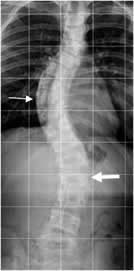

MEDICIONES ESCOLIOSIS.

La escoliosis se define como una curvatura espinal lateral en el plano coronal, con un ángulo de Cobb mayor de 10º. Un ángulo menor de 10º, asintomático y que no progresa, se conoce como asimetría espinal o curvatura y no escoliosis. (3, 5, 25, 26). (Fig 10).

Fig 10. Asimetría espinal.

A y B: Rx AP. Desviación en los ejes de la columna. En A dorsal derecha y en B lumbar izquierda, pero de poca magnitud por asimetría.